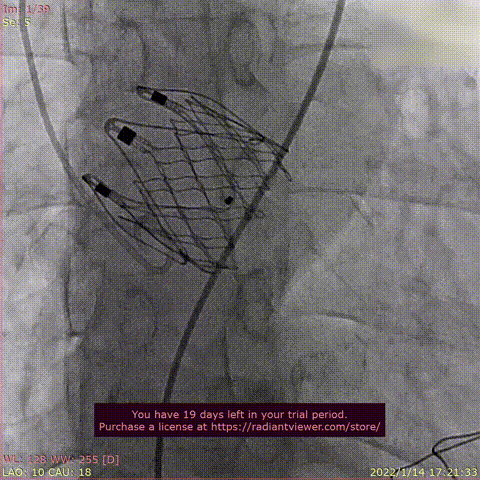

患者为72岁男性,因“反复心累气紧10月余,加重半年 “主诉入院。术前超声提示左室肥大,双房增大,主动脉增宽,LVEF 37%,主动脉瓣重度反流。术后即刻主动脉瓣大量反流消失,平均跨瓣压差显著降低为4 mmHg,心功能显著改善。

瓣膜释放过程